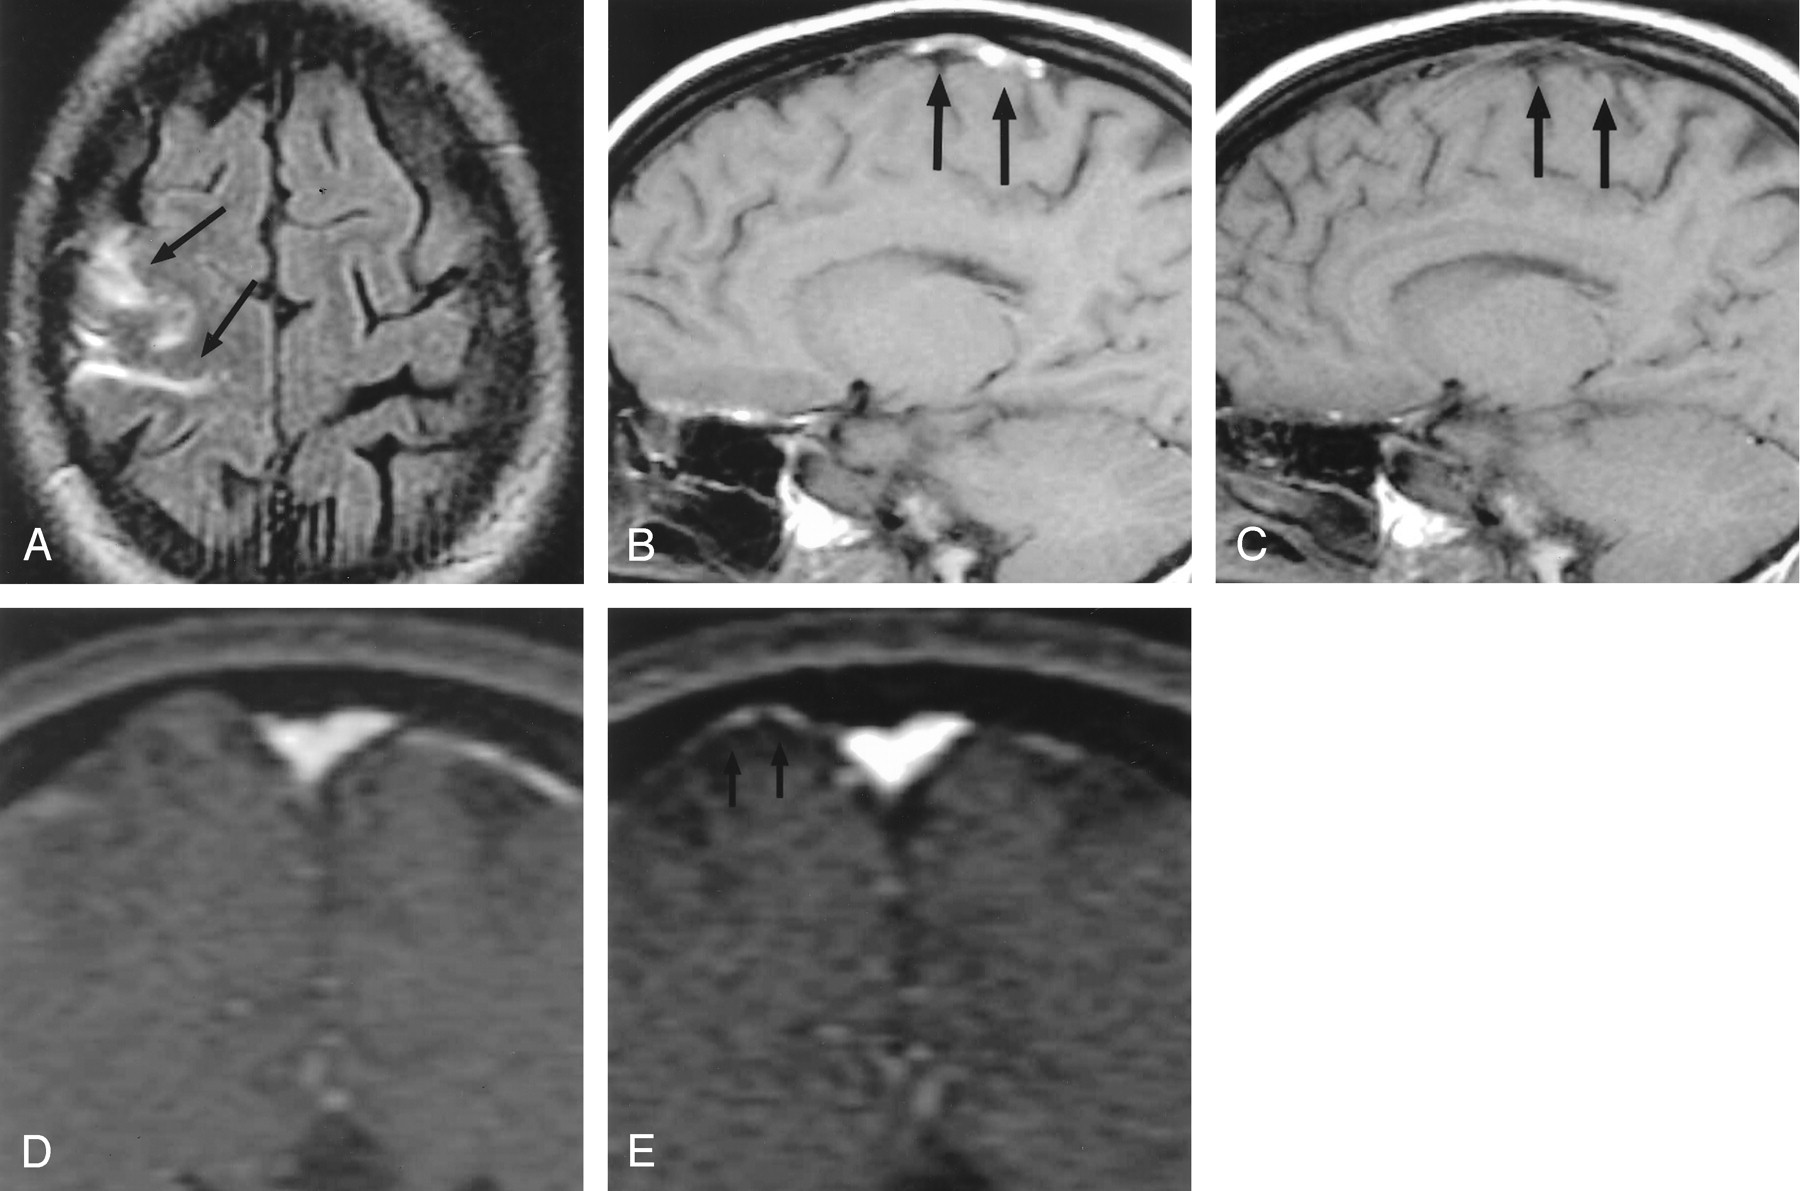

Patient 1, a 29-year-old woman with headaches, seizures, and cortical venous thrombosis.

A, Axial FLAIR (10,002/158/2200) [TR/TE/TI] MR image shows focal sulcal hyperintensity at the right frontoparietal convexity (arrows).

B, Right parasagittal T1-weighted (500/14) MR image shows tubular hyperintense thrombus (arrows) in a right convexity cortical vein, probably the vein of Trolard.

C, Right parasagittal T1-weighted (500/14) MR image, obtained approximately 3 months after the FLAIR image in panel A, shows resolution of the hyperintense thrombus (arrows).

D and E, Source data from MR venograms obtained at presentation (D) and approximately 3 months later (E) show interval appearance of flow signal intensity (arrows) in the previously occluded cortical vein.

Follow-up MR imaging was obtained approximately 3 months after the patient’s initial presentation. This examination showed interval resolution of the clot in the cortical vein (Fig 1C). In addition, partial recanalization of the thrombosed cortical vein was noted on MR venography (Figs 1D and E).